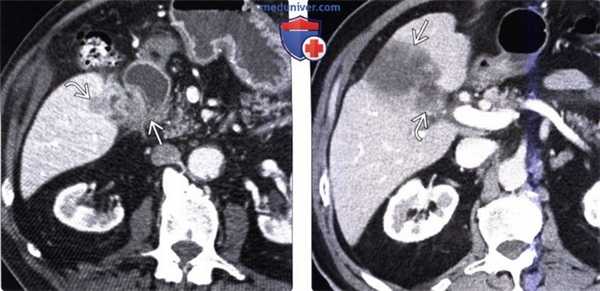

(Слева) На аксиальной КТ с контрастным усилением у пациента, страдающего меланомой, визуализируется метастаз в желчном пузыре, а также крупный вторичный очаг округлой формы в нижней доле левого легкого. Меланома чаще всего дает метастазы в желчный пузырь.

(Справа) На сонограмме (цветовая допплерография) в желчном пузыре визуализируется округлый гипоэхогенный узел с признаками наличия кровотока внутри него. В этом случае доказан метастаз меланомы, хотя изменения могут быть обусловлены также раком желчного пузыря или большим полипом. (Слева) На аксиальной КТ с контрастным усилением у пациента с желтухой, предъявляющего жалобы на снижение веса тела, в желчном пузыре визуализируются камни и мягкотканное образование. Обратите также внимание на выраженную лимфаденопатию. И объемное образование, и увеличение лимфо узлов обусловлены неходжкинской лимфомой.

(Справа) На корональной КТ с контрастным усилением визуализируется плохо различимый мягкотканный узел в общем желчном протоке, стенка проксимальных протоков утолщена и интенсивно накапливает контраст. Эти изменения могут быть вызваны холангиокарциномой, но в этом случае обусловлены метастазом рака толстой кишки.